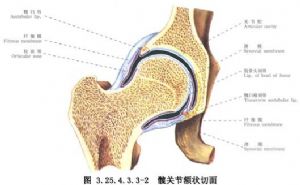

7.2 2.髖臼成形

切開關節囊,於關節囊上做截骨術,弧形截骨線距髖臼緣周圍0.5cm,將其上2/3呈弧形切開,用弧形髖關節成形鑿,將髖臼向下外翻,形成的骨缺損,用取自髂骨的骨塊嵌入修補。